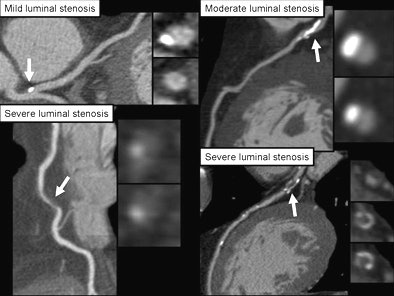

In the study, Weill researchers graded each stenosis found at 64-slice coronary CTA as minimal (< 30%), mild (30% to 49%) or severe (≥ 70%). A modified Duke coronary artery jeopardy score (originally designed for invasive coronary angiography) was also used to evaluate plaque in the right coronary artery, left anterior descending artery, left circumflex artery, and left main artery.

| Each stenosis detected at coronary CTA was graded as minimal (< 30%), mild (30% to 49%), or severe (≥ 70%). All images courtesy of Dr. James Min. |